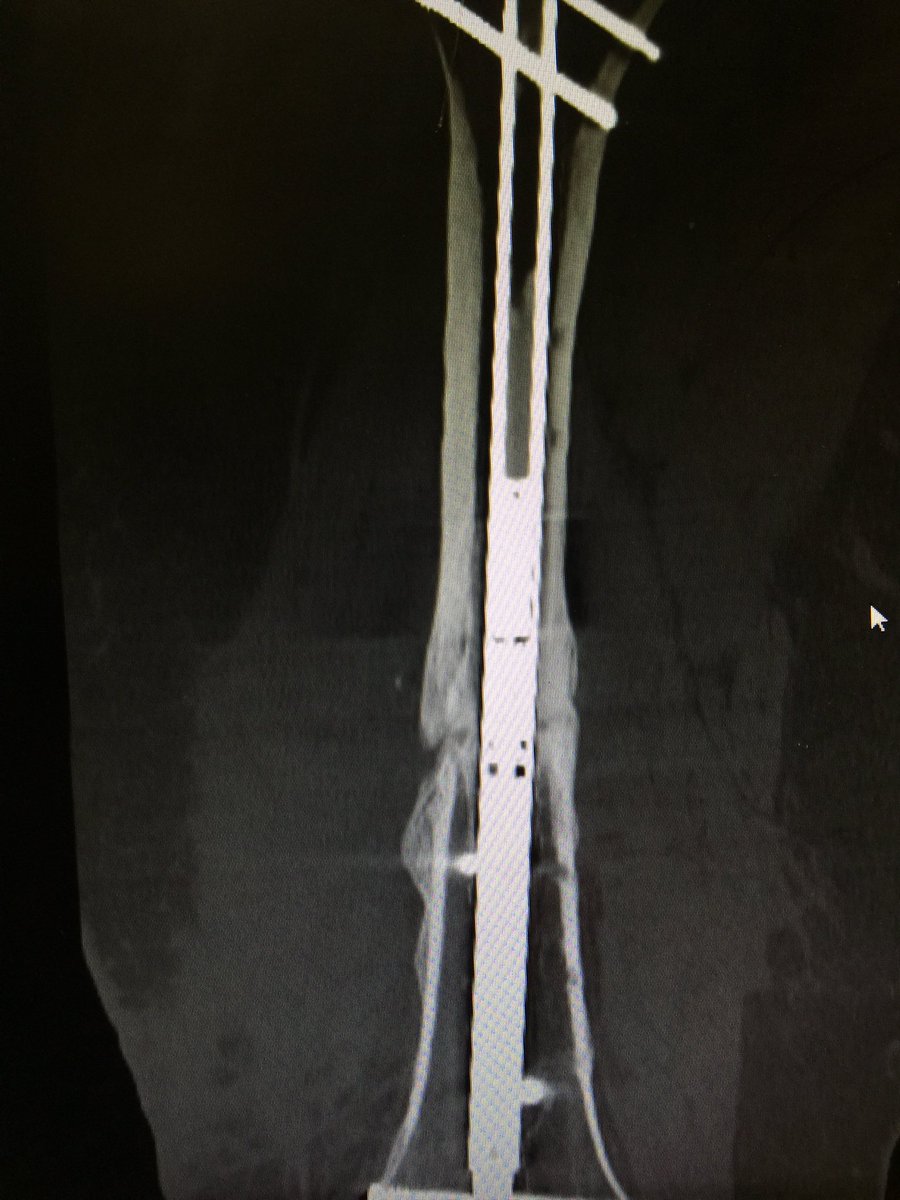

#Precice#Unyte crushes it again. Another nasty nonunion compressed into healing with the internal compression nail. This is amazing.pic.twitter.com/nhoUkQ3lU6